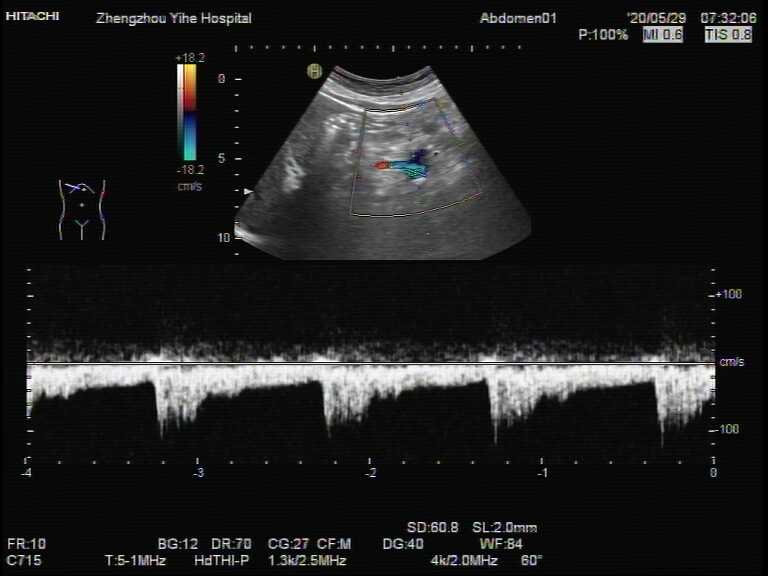

经过我们彩超医生细致耐心的检查,依据血管的来源及走形方向,发现这个包块其实是一支细窄的血管,局部呈囊状扩张,接近正常血管宽度的4倍以上(图3、4)。根据种种迹象表明它可能是脾动脉瘤。

图3